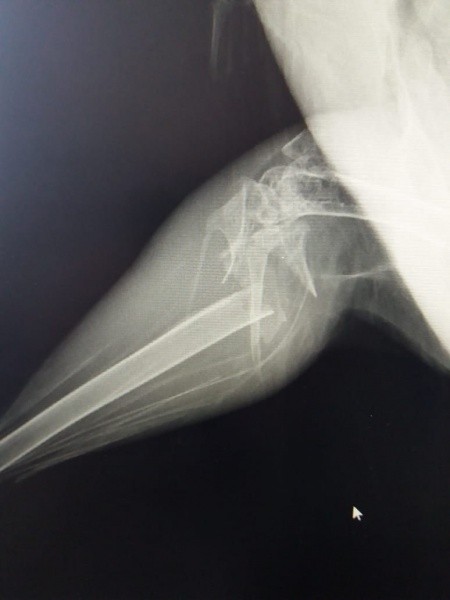

На Йошкар-Олинскую городскую станцию по борьбе с болезнями животных привезли фазана, который повредил лапку, когда его пытались поймать. Рентген показал, что у пернатого пациента - оскольчатый перелом голени. Ветеринарный хирург Юрий Волков провел операцию методом остеосинтеза на внешнем фиксаторе.

Фото Йошкар-Олинской станции по борьбе с болезнями животных